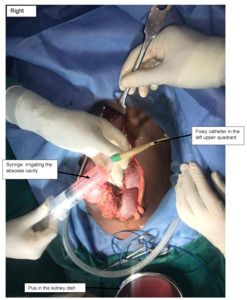

The patient was informed of the options of preserving the spleen (using available catheter drainage) and splenectomy with its complications. The patient consented to a laparotomy under general anaesthesia, and 2 L of yellowish pus were drained from the abdominal cavity (Figure 2). There was a single large loculated abscess in the superior pole of the spleen with a 1-2 cm opening on the superior border. The pus actively oozed out into the peritoneal cavity and was drained without debriding the spleen. The pus was drained with the readily available 14 French Foley catheter (Figure 3). The catheter was balloon-supported and secured to the skin in the left upper quadrant. The rest of the spleen appeared normal. The left kidney appeared enlarged, while the right kidney was not found in the normal anatomical position (ectopic pelvic kidney). Peritoneal lavage with copious amounts of warm saline and irrigation of the splenic abscess cavity were performed (Figure 4).

In our study, upon exploratory laparotomy, a huge ruptured splenic abscess with pyoperitoneum was found. The readily available 14 French Foley catheter was used to drain the splenic abscess and lavage. The use of catheter drainage is commendable in unilocular abscesses, non-septated abscesses, low-resource regions, and young patients, where you want to preserve the spleen.7 As such, a splenectomy was not done in our case. Furthermore, the high cost of the post-splenectomy vaccines, unavailability of prophylactic medications/vaccines, and poor patient education aided in guiding the option to preserve the spleen in this case.